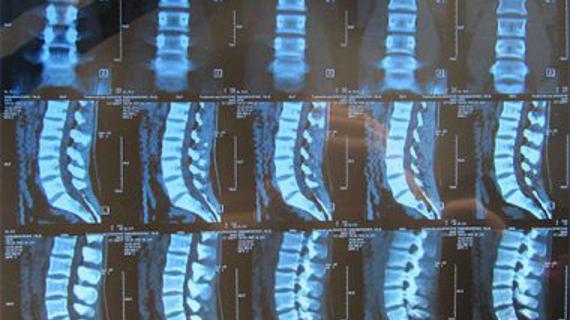

Дегенеративные заболевания позвоночника являются распространенной патологией, поражающей пациентов различных возрастных групп. В основе лежит нарушение питания костных и хрящевых...